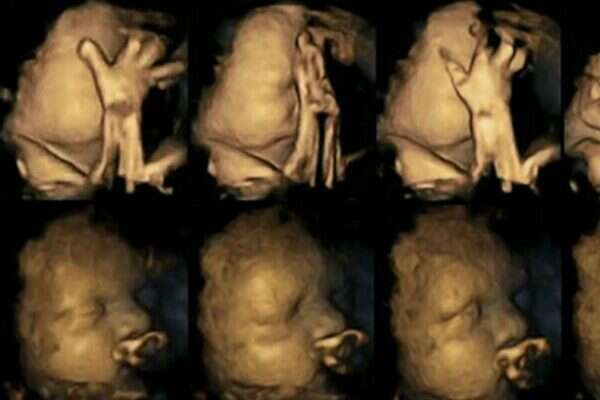

ההשפעות של עישון על ילדיכם ידועות, אבל ישנה קבוצה של מדענים שמאמינים כי הם יכולים להציג את ההשלכות של עישון עוד במהלך ההיריון. חוקרים עשו שימוש בטכנולוגיית D4 באולטרסאונד על מנת לייצר תמונות של עובר לאישה מעשנת. רופאים רבים מפצירים בנשים בהריון להפסיק לעשן בשל העלאת הסיכון ללידה מוקדמת, בעיות נשימה ואפילו מוות בחלק מן המקרים. כעת, מקווים החוקרים שהתמונות הללו יעודדו אימהות שנאבקות להפסיק לעשן.

ד"ר נדיה רייסלנד עשתה שימוש בטכנולוגיה מתקדמת על מנת לנהל רישומים של מאות תזוזות של עוברים ברחם. היא עקבה אחר 20 אימהות בבית חולים במידלסבורו, אנגליה. ארבע מהאימהות עישנו מספר ממוצע של 14 סיגריות ביום. לאחר שבחנה את סריקות התמונות שיצאו בשלבי ה-24, 28, 32 ו-36 שבועות להריון, היא גלתה שהעוברים של האימהות המעשנות נגעו בעצמם והזיזו את פיהם באופן מובהק, הרבה יותר מהעוברים של האימהות הלא מעשנות.

עוברים בדרך כלל נוגעים בעצמם ומזיזים את פיהם, אך ככל שהם גדלים הם גם הולכים ונפטרים מזה ומפסיקים בתזוזות. המסקנה מהנתונים של המחקר היא שהעוברים לאימהות מעשנות לא הפסיקו את תדירות התזוזות, דבר המצביע על היעדר התפתחות של המערכת העצבית. ד"ר רייסלנד מדגישה: "צריך להרחיב את המחקר בכדי לאשש את התוצאות שלו".

החוקרת מאמינה שההבדלים בין התצלומים, שמראים הבדלים ברורים, יכולים לסייע לאימהות להפסיק לעשן. עם זאת, היא מתנגדת לחלוטין להפוך אימהות שלא מצליחות לעשן לאנשים רעים והדגישה כי חייבים לעזור להם להפסיק ולתת להם תמיכה ראויה. למרות תוצאות המחקר כל התינוקות שהשתתפו בו נולדו בגודל ומשקל תקינים.